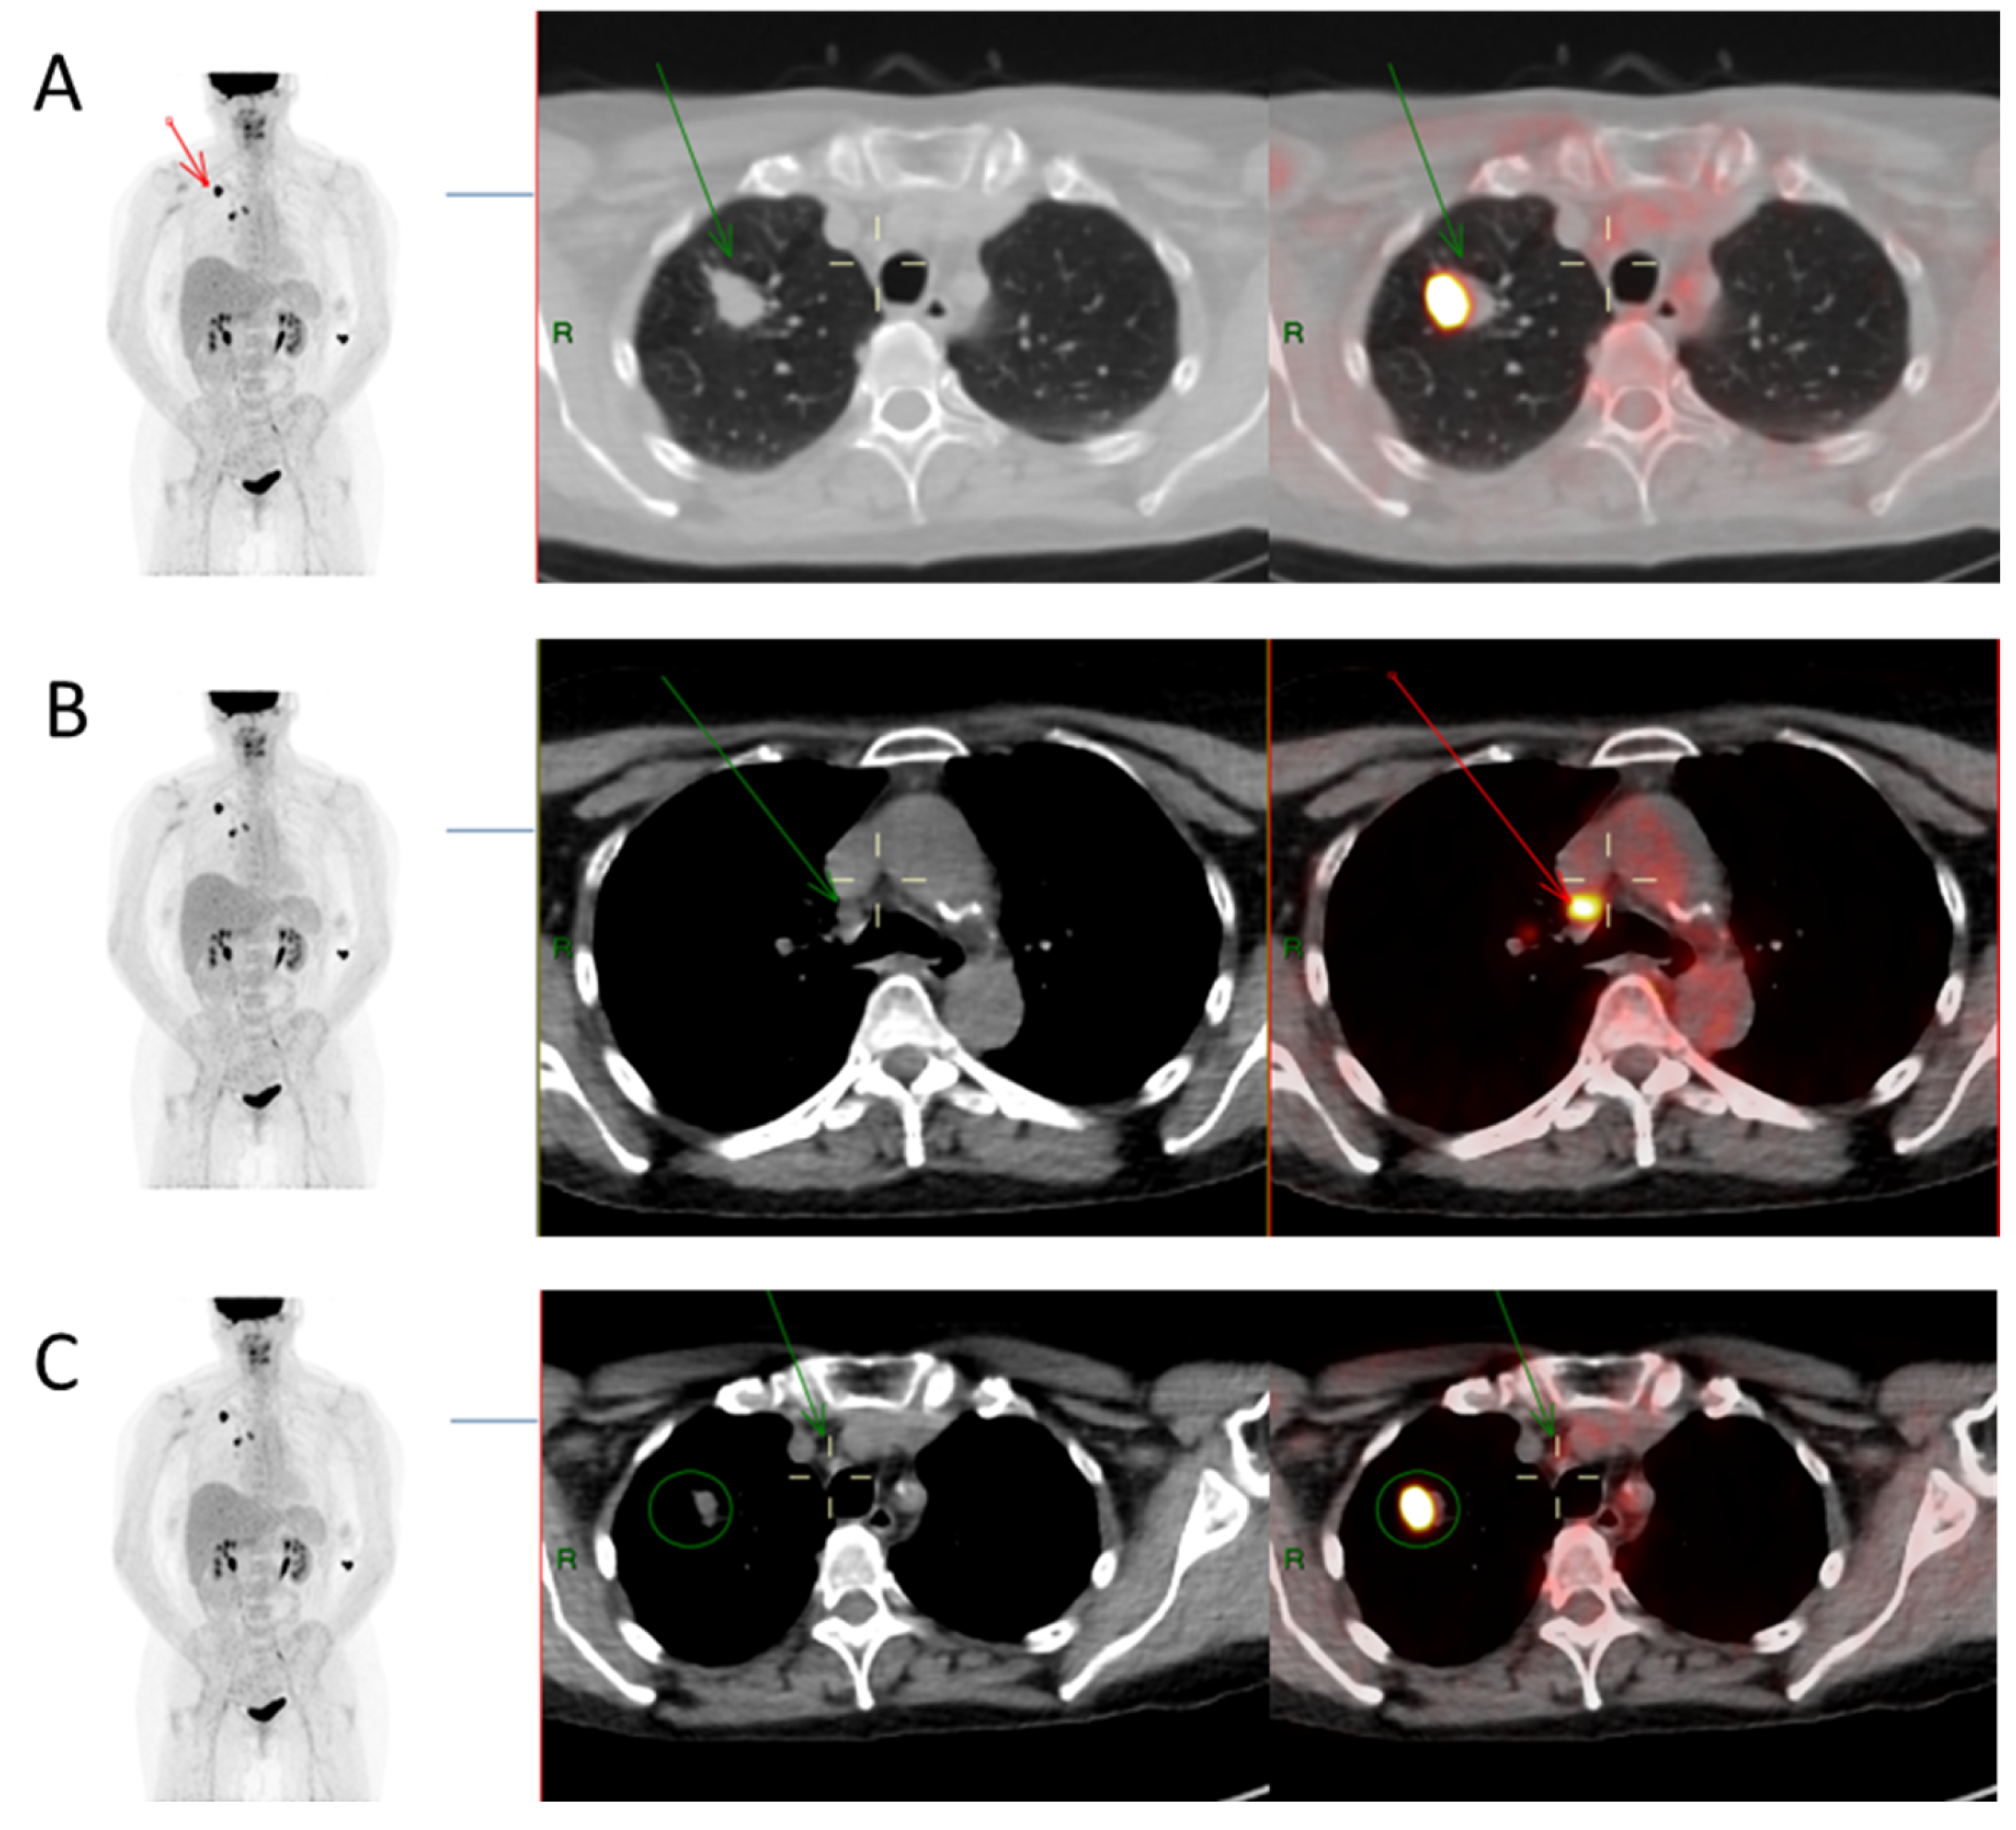

From www.intechopen.com

Figure 3. Pet/Ct Imaging In Different Types Of Lung Cancer An Overview Lung cancer (lc) still represents one of the most common tumours in both women and men. This review article aimed to summarize the basic principles, indications, cancer staging considerations, and future. Pet/ct imaging in different types of lung cancer: In this paper, we review the current developments, potential applications, limitations, and perspectives of pet/ct radiomics with specific focus on the. Pet/Ct Imaging In Different Types Of Lung Cancer An Overview.